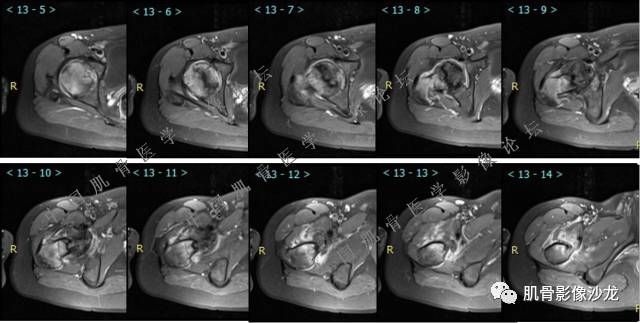

主诉:右大腿疼痛、活动受限20天

现病史:患者于20天前无明显诱因出现右下肢疼痛,活动受限,疼痛呈阵发性,活动后加重。自行口服止痛药芬必得,效果不佳,至当地医院治疗,检查发现右侧股骨近端病变。遂来诊

葛英霖 20:30 原发或继发动脉瘤样骨囊肿,继发于巨细胞瘤,软骨母,纤维组织细胞瘤,骨母等等

向以四 20:30 软骨母合并ABC,

医影在线 20:30 软骨母,/继发ABC

飞鹰行动 20:31 T2信号高,有软骨成分

Echo 20:32 T2确实有一块区域很亮 ,并有野液平

飞鹰行动 20:33 有侵袭性

飞鹰行动 20:35 骨皮质破坏,周围骨质异常信号

葛英霖 20:36 这不是良性病变

葛英霖 20:36 中间型可能性极大

葛英霖 20:37 明显侵蚀骨内膜啊,硬化边也不完整 (细箭头所示)

葛英霖 20:43 提不提也很明显继发了abc

葛英霖 20:44 是

葛英霖 20:46 明显的多囊状改变,液液平面